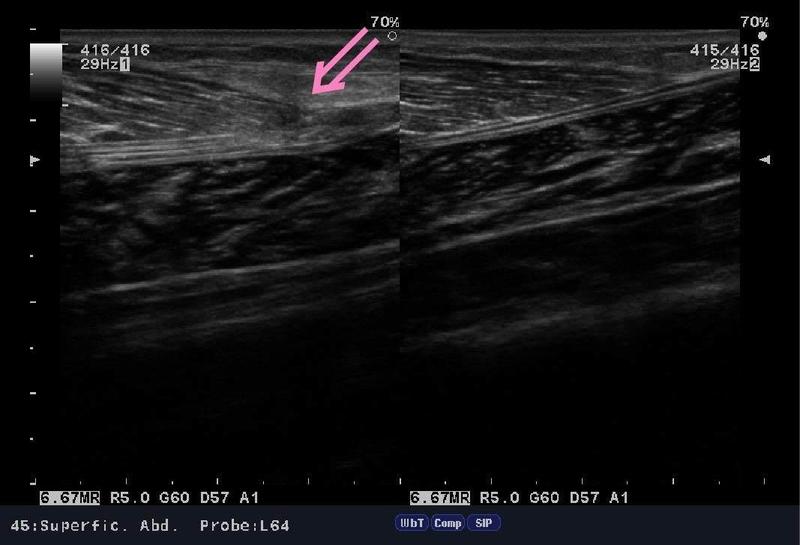

「まる接骨院」では"肉離れ"の治療、

アキュースコープ・マイオパルスという治療器を使用して、

行っていくのですが、正直、復帰・回復はかなり早いです。